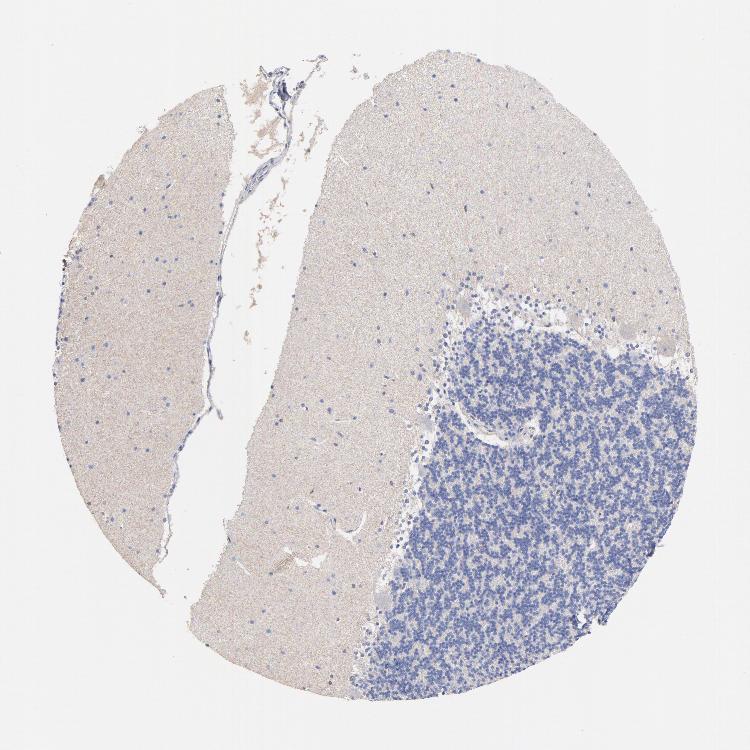

CEREBELLUM - Antibody stainingi

Antibody staining in the annotated cell types in the current human tissue is reported as not detected, low, medium, or high, based on conventional immunohistochemistry profiling in selected tissues. This score is based on the combination of the staining intensity and fraction of stained cells.

Each image is clickable and will lead to virtual microscopy that enables deeper exploration of all samples and also displays staining intensity scores, fraction scores and subcellular localization as well as patient and tissue information for each sample.

Antibody HPA016646Antibody CAB003696

Purkinje cells Not detectedNot detected

Cells in granular layer Not detectedNot detected

Cells in molecular layer Not detectedLow